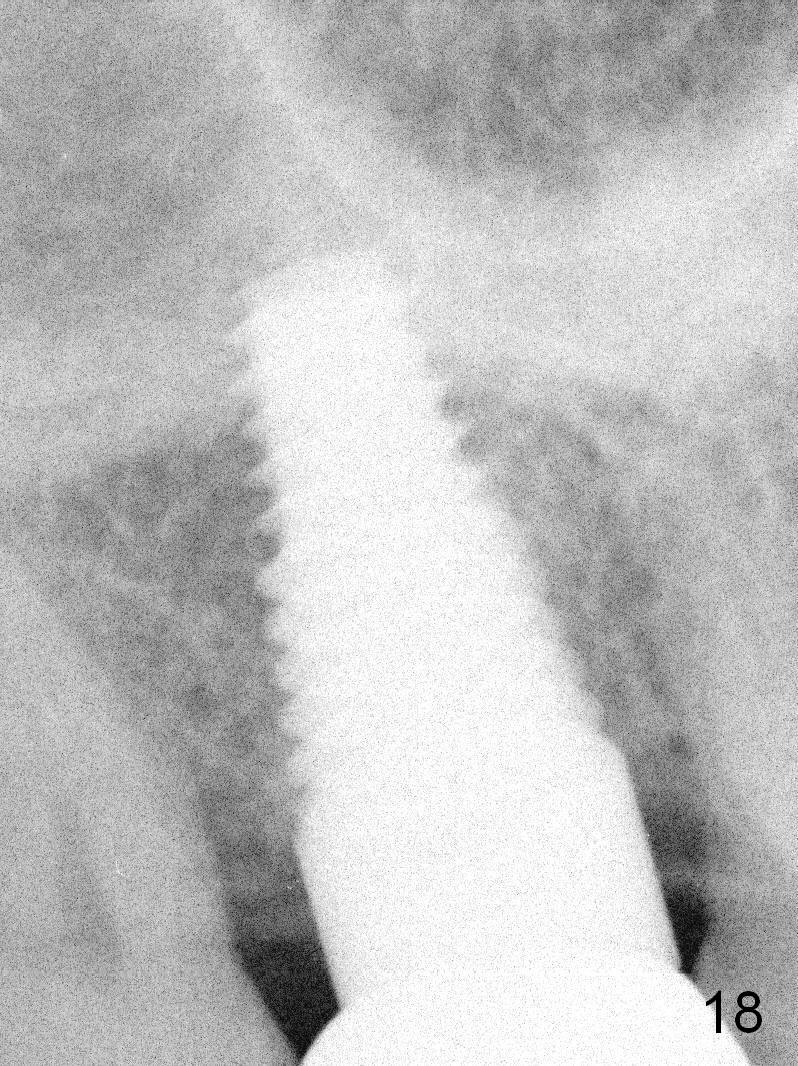

A 65-year-old lady is at early stage of Parkinson's disease and appears to be a bruxer. There are multiple chipped teeth, including #2 (Fig.1,4 *). She chooses implant over RCT retreat. A tissue-level implant (Fig.2) matches the root shape of the affected tooth better than a bone-level one (Fig.3), because of taper. The buccopalatal and mesiodistal dimensions of the extraction socket are 11 and 8 mm, respectively (Fig.5,7).

The buccal roots are fused. The buccal socket (BS) seems to be larger than the palatal one (PS). There is a septum (S) between the 2 sockets. Both the buccal and palatal plates (BP, PP) are intact. The anatomy is illustrated in Fig.6a (buccopalatal section) with the same abbreviations, mentioned above. SF: sinus floor.

Osteotomy for immediate implant is initiated with a 2 mm pilot drill (Fig.6b red arrow) in the coronal end of the buccal slope of the septum (center of the socket). Once the drill gets initial penetration, the trajectory changes to the long axis of the tooth (Fig.6c). Then PA is taken with a parallel pin (Fig.7). It appears that the depth is not enough; there is bone apical to the pin. As osteotomy increases in diameter, burs may be deviated buccally due to the septal buccal slope (to be discussed below). With longer osteotomy, the deviation may be less. Osteotomy is deepened (Fig.6d). From this moment on, nose blowing test is done after each step. The result is all negative. As drill diameter increases, they do deviate buccally (Fig.6e arrow), since there is less bone contact buccally than lingually (compare Fig.6e,f). With the same reason, smaller tapered taps (Fig.6g pink, 5 and 6 mm) tend to be mobile buccally (arrow). When a large tap (7 mm) is inserted (Fig.8), there is no buccal mobility. It appears that the tap contacts more of the buccal plate (Fig.6h), but the coronal end of the tap is buccal (Fig.6i, pink circle). At each step of osteotomy, the coronal end of a bur or tap should be pushed as lingual as possible so that the final tap is favorable for restoration (Fig.6j). Sinus lift is done (Fig.6k red circle; Fig.9 *) before placement of 7x17 mm implant (I, >60 Ncm). Since the palatal socket is not associated with implant stability, it is closed by collagen plug (Fig.6l, blue area). As extra precaution, bone graft is placed around the coronal portion of the tissue-level implant (Fig.6l red circles), followed by collagen dressing.